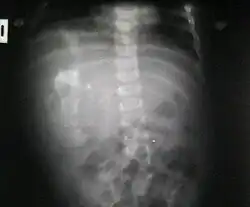

Fetus in fetu

Fetus in fetu (or foetus in foetu) is a rare developmental abnormality in which a mass of tissue resembling a fetus forms inside the body of its twin. An early example of the phenomenon was described in 1808 by George William Young.[1]

There are two hypotheses for the origin of a fetus in fetu. One hypothesis is that the mass begins as a normal fetus but becomes enveloped inside its twin.[2] The other hypothesis is that the mass is a highly developed teratoma. Fetus in fetu is estimated to occur in 1 in 500,000 live births.[3]

Fetus in fetu may be a parasitic twin fetus growing within its host twin. Very early in a monozygotic twin pregnancy, in which both fetuses share a common placenta, one fetus wraps around and envelops the other. The enveloped twin becomes a parasite, in that its survival depends on the survival of the host twin, by drawing on the host twin's blood supply. The parasitic twin is anencephalic (without a brain) and lacks some internal organs, and as such is unable to survive on its own.